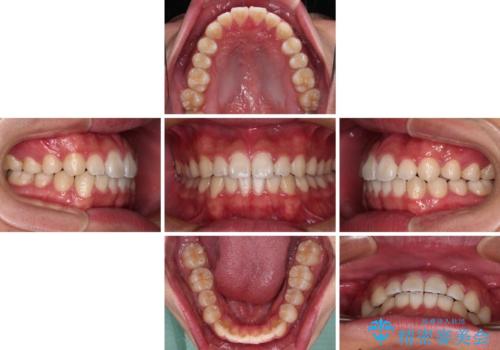

- 20代男性

- インビザライン・ライト

- 8ヶ月

- 上下前歯の叢生を気にして来院された患者様です。

費用を抑え、期間もあまりかけずに治療をしたいとのことで、インビザライン・ライトを用いて矯正治療を行うこととしました。